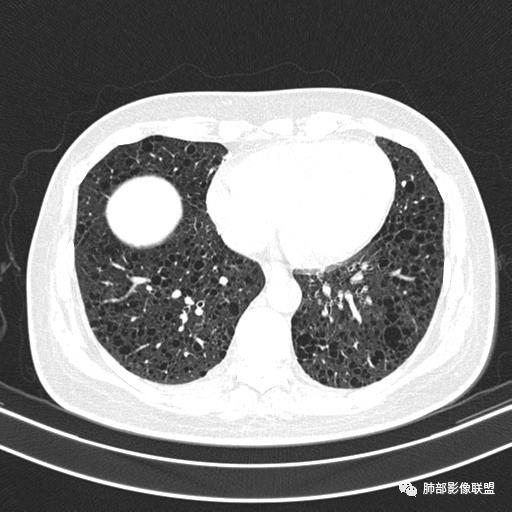

中年女性,不吸烟

双肺弥漫囊腔,累及肋膈角,囊腔形态相对规则单一。

CT平扫示双肺弥漫分布大小不等囊状薄壁透光区,无内、中、外带分布差异,间质稍示增厚。拟LAM

中年女性育龄期妇女,咳嗽气喘,无吸烟史,有苯吸入史。影像:双肺弥漫均匀小囊腔,无明显分布优势,囊腔形态欠规则,壁薄,部分囊腔边缘血管征,伴双肺弥漫磨玻璃影,无结节,考虑lam,鉴别苯中毒肺损伤,囊腔多有分布优势,小叶中心分布为主,形态规整等

女,46,活动性气喘1年。苯吸入史半年。胸部CT:两肺弥漫囊腔,上至肺尖,下至肋膈角,形态类似小囊腔。考虑:LAM,鉴别LIP,BHD,PLCH等。

双肺弥漫大小不一薄壁含气囊腔,囊间肺组织正常,正常肺背景,肺尖肺底受累;青年女性,气喘,支持LAM

双肺多发大小相近的囊状影,分布趋势趋于一致,中年女性,考虑LAM。部分囊内见血管及分隔影,小叶中心性肺气肿代排

CT表现:双肺弥漫大小不等的薄壁囊腔,囊壁<2mm,外形规则,血管影多位于囊腔周围,囊腔之间肺组织正常,随着疾病进展到晚期,囊腔变大、增多,不可胜数,囊腔可融合成较大的囊,与肺气肿相似,形成间质性肺纤维化。部分病例可出现结节影。